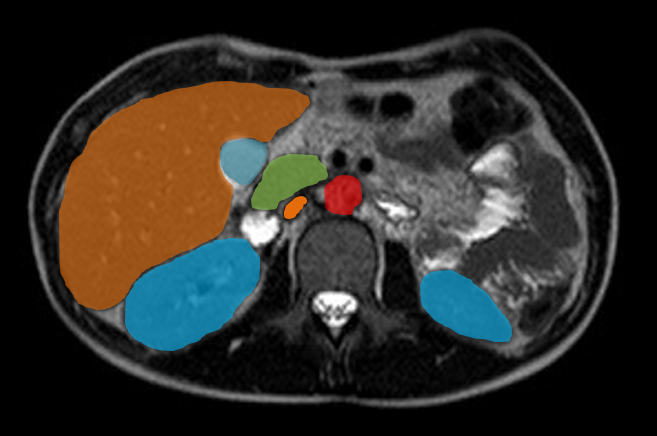

Inteventionelle Radiologie-Teil der Diagnostischen Radiologie oder ein eigenständiges Fachgebiet?

Die Entwicklung und Integration der interventionellen Radiologie im klinischen Alltag wird weltweit unterschiedlich gehandhabt. Während sie in den USA bereits als eigenständiges Fachgebiet anerkannt ist, gilt sie in Deutschland nach wie vor als fakultatives Teilgebiet innerhalb der Radiologie.

In der interventionellen Radiologie beschränkt sich die Tätigkeit des Radiologen nicht allein auf die bildgebende Diagnostik. Vielmehr übernimmt er eigenständig minimalinvasive Eingriffe und trägt dabei die Verantwortung für die prä-, peri- und postoperative Versorgung der Patient: innen.

Mit diesem Wahlfach möchten wir Ihnen praxisnahe Einblicke in das vielseitige und verantwortungsvolle ärztliche Arbeiten in der interventionellen Radiologie ermöglichen.